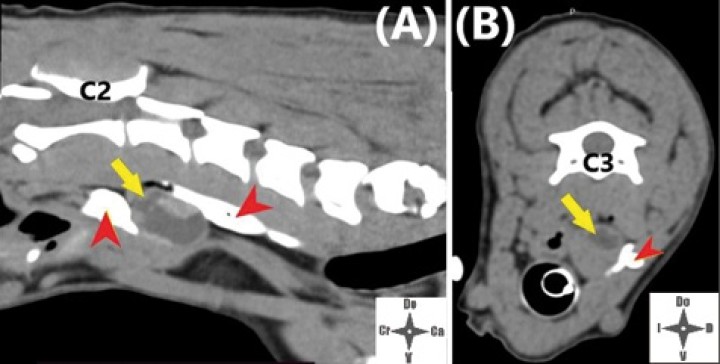

<p>Imagen de TC con contraste IV; la fecha amarilla señala la neoplasia.</p>

Imagen de TC con contraste IV; la fecha amarilla señala la neoplasia.

Las neoplasias tiroideas representan aproximadamente entre el 1,2 y el 3,8 % de las neoplasias caninas,[ Liptak JM: Canine thyroid carcinoma. Clin Tech Small Anim Pract. 2007; 22(2): 75-81. [pubMed] ] siendo los carcinomas más comunes que los adenomas. Los carcinomas tiroideos se caracterizan por su rápido crecimiento y es probable su invasión a tejidos adyacentes como laringe, tráquea, arteria carótida o vena yugular, entre otras estructuras, lo cual es parte de la pesquisa previa para establecer el estadío de la neoplasia.[ Prastiti E, Tzenetidou Z, Papazoglou, LG: Canine thyroid tumours: diagnosis and treatment. Hellenic Journal of Companion Animal Medicine 2018; 7(2): 8-27. ] En el presente caso se realizó previamente una tomografía computarizada (TC) en la que se observó que el tamaño de la neoplasia era de 1,6 x 1,5 x 2,5 centímetros. Seguidamente, se inyectó contraste intravenoso para evaluar el comportamiento invasivo de la neoplasia, no observándose invasión aparente hacia los tejidos adyacentes como tampoco signos de metástasis pulmonar.

Con el fin de evitar el uso de opioides, se planificó una ALO cuya premedicación consistió en dexmedetomidina (Dexmopet, Fatro, Barcelona) 8 µg/kg vía intramuscular, considerando el carácter nervioso y excitable del paciente. A los 15 minutos se canalizó la vena cefálica (Sterican 22G x 1, BBraun vetcare, Barcelona), previa preoxigenación, y la anestesia se indujo con 3,5 mg/kg de propofol intravenoso (IV) (Propofol Lipuro, BBraun Vetcare, Barcelona). El mantenimiento anestésico se realizó con sevoflurano (SevoFlo, Zoetis, Louvain-la-Neuve) (concentración de sevoflurano espirada entre 1,7-2,0) empleando una FiO2 de 0,5 y ventilación espontánea. Se monitorizó la pulsioximetría, temperatura, ECG, capnografía, presión arterial no invasiva (PANI) y espirometría mediante un monitor multiparamétrico (5S Datex-Ohmeda, Finlandia). Se planeó realizar una TC prequirúrgica para volver a valorar la masa antes de comenzar la cirugía. Aprovechando esta circunstancia, se colocó al paciente en decúbito lateral izquierdo, depilando la región cervical, y se procedió a realizar un bloqueo anestésico ecoguiado empleando un ecógrafo portátil (Sonosite M-turbo, Sonosite, EUA) con sonda lineal 10-15 MHz posicionada inmediatamente ventral al ala del atlas en sentido longitudinal a la columna cervical (Figs. 2 y 3). Se localizaron las raíces ventrales cervicales de C2 y C3, las cuales se visualizan en el plano interfascial entre los músculos omotransverso e intertransversos, como engrosamientos de este, siendo dichas raíces estructuras elipsoidales con un halo hiperecoico y su centro hipoecoico. La neoplasia se encontraba próxima al sitio de inyección (Fig. 4). Se realizó un abordaje en plano y se inyectó una mezcla de bupivacaína (Bupivacaine, BBraun, Barcelona) 0,5 % con contraste iodado (Ultravist 300, Berlimed S.A, Alcalá de Henares) en una proporción de 4:1, a razón de 0,15 ml/kg alrededor del espacio interfascial de C2, confirmando la hidrodisección de este plano (Fig. 4). Además, se realizó la inyección contralateral subcutánea en las ramas ventrales superficiales de C2, que se localizan anatómicamente aproximadamente entre 0,5 y 1 cm dorsal a la bifurcación de la vena yugular en la grasa subcutánea profunda al platisma, utilizando 0,1 ml/kg de bupivacaína 0,5 % (Fig. 5). Dichos bloqueos se realizaron tras un exhaustivo estudio de la anatomía de la región, el reconocimiento cadavérico de dichas estructuras y empleando como referencia tanto el bloqueo descrito en equinos como el bloqueo intermedio del plexo cervical descrito en humanos. Se utilizó una aguja espinal (Spinocan Quincke 22 gauge, BBraun, Barcelona). Una vez realizado el bloqueo se repitió inmediatamente otra TC para evaluar la distribución de la solución inyectada (Figs. 6 y 7).

<p>Imágenes de TC post-inyección. (<strong>A</strong>) Corte sagital. (<strong>B</strong>) Corte axial. La flecha amarilla marca la neoplasia y las cabezas de flecha rojas el contraste en el espacio interfascial.</p>

Imágenes de TC post-inyección. (A) Corte sagital. (B) Corte axial. La flecha amarilla marca la neoplasia y las cabezas de flecha rojas el contraste en el espacio interfascial.